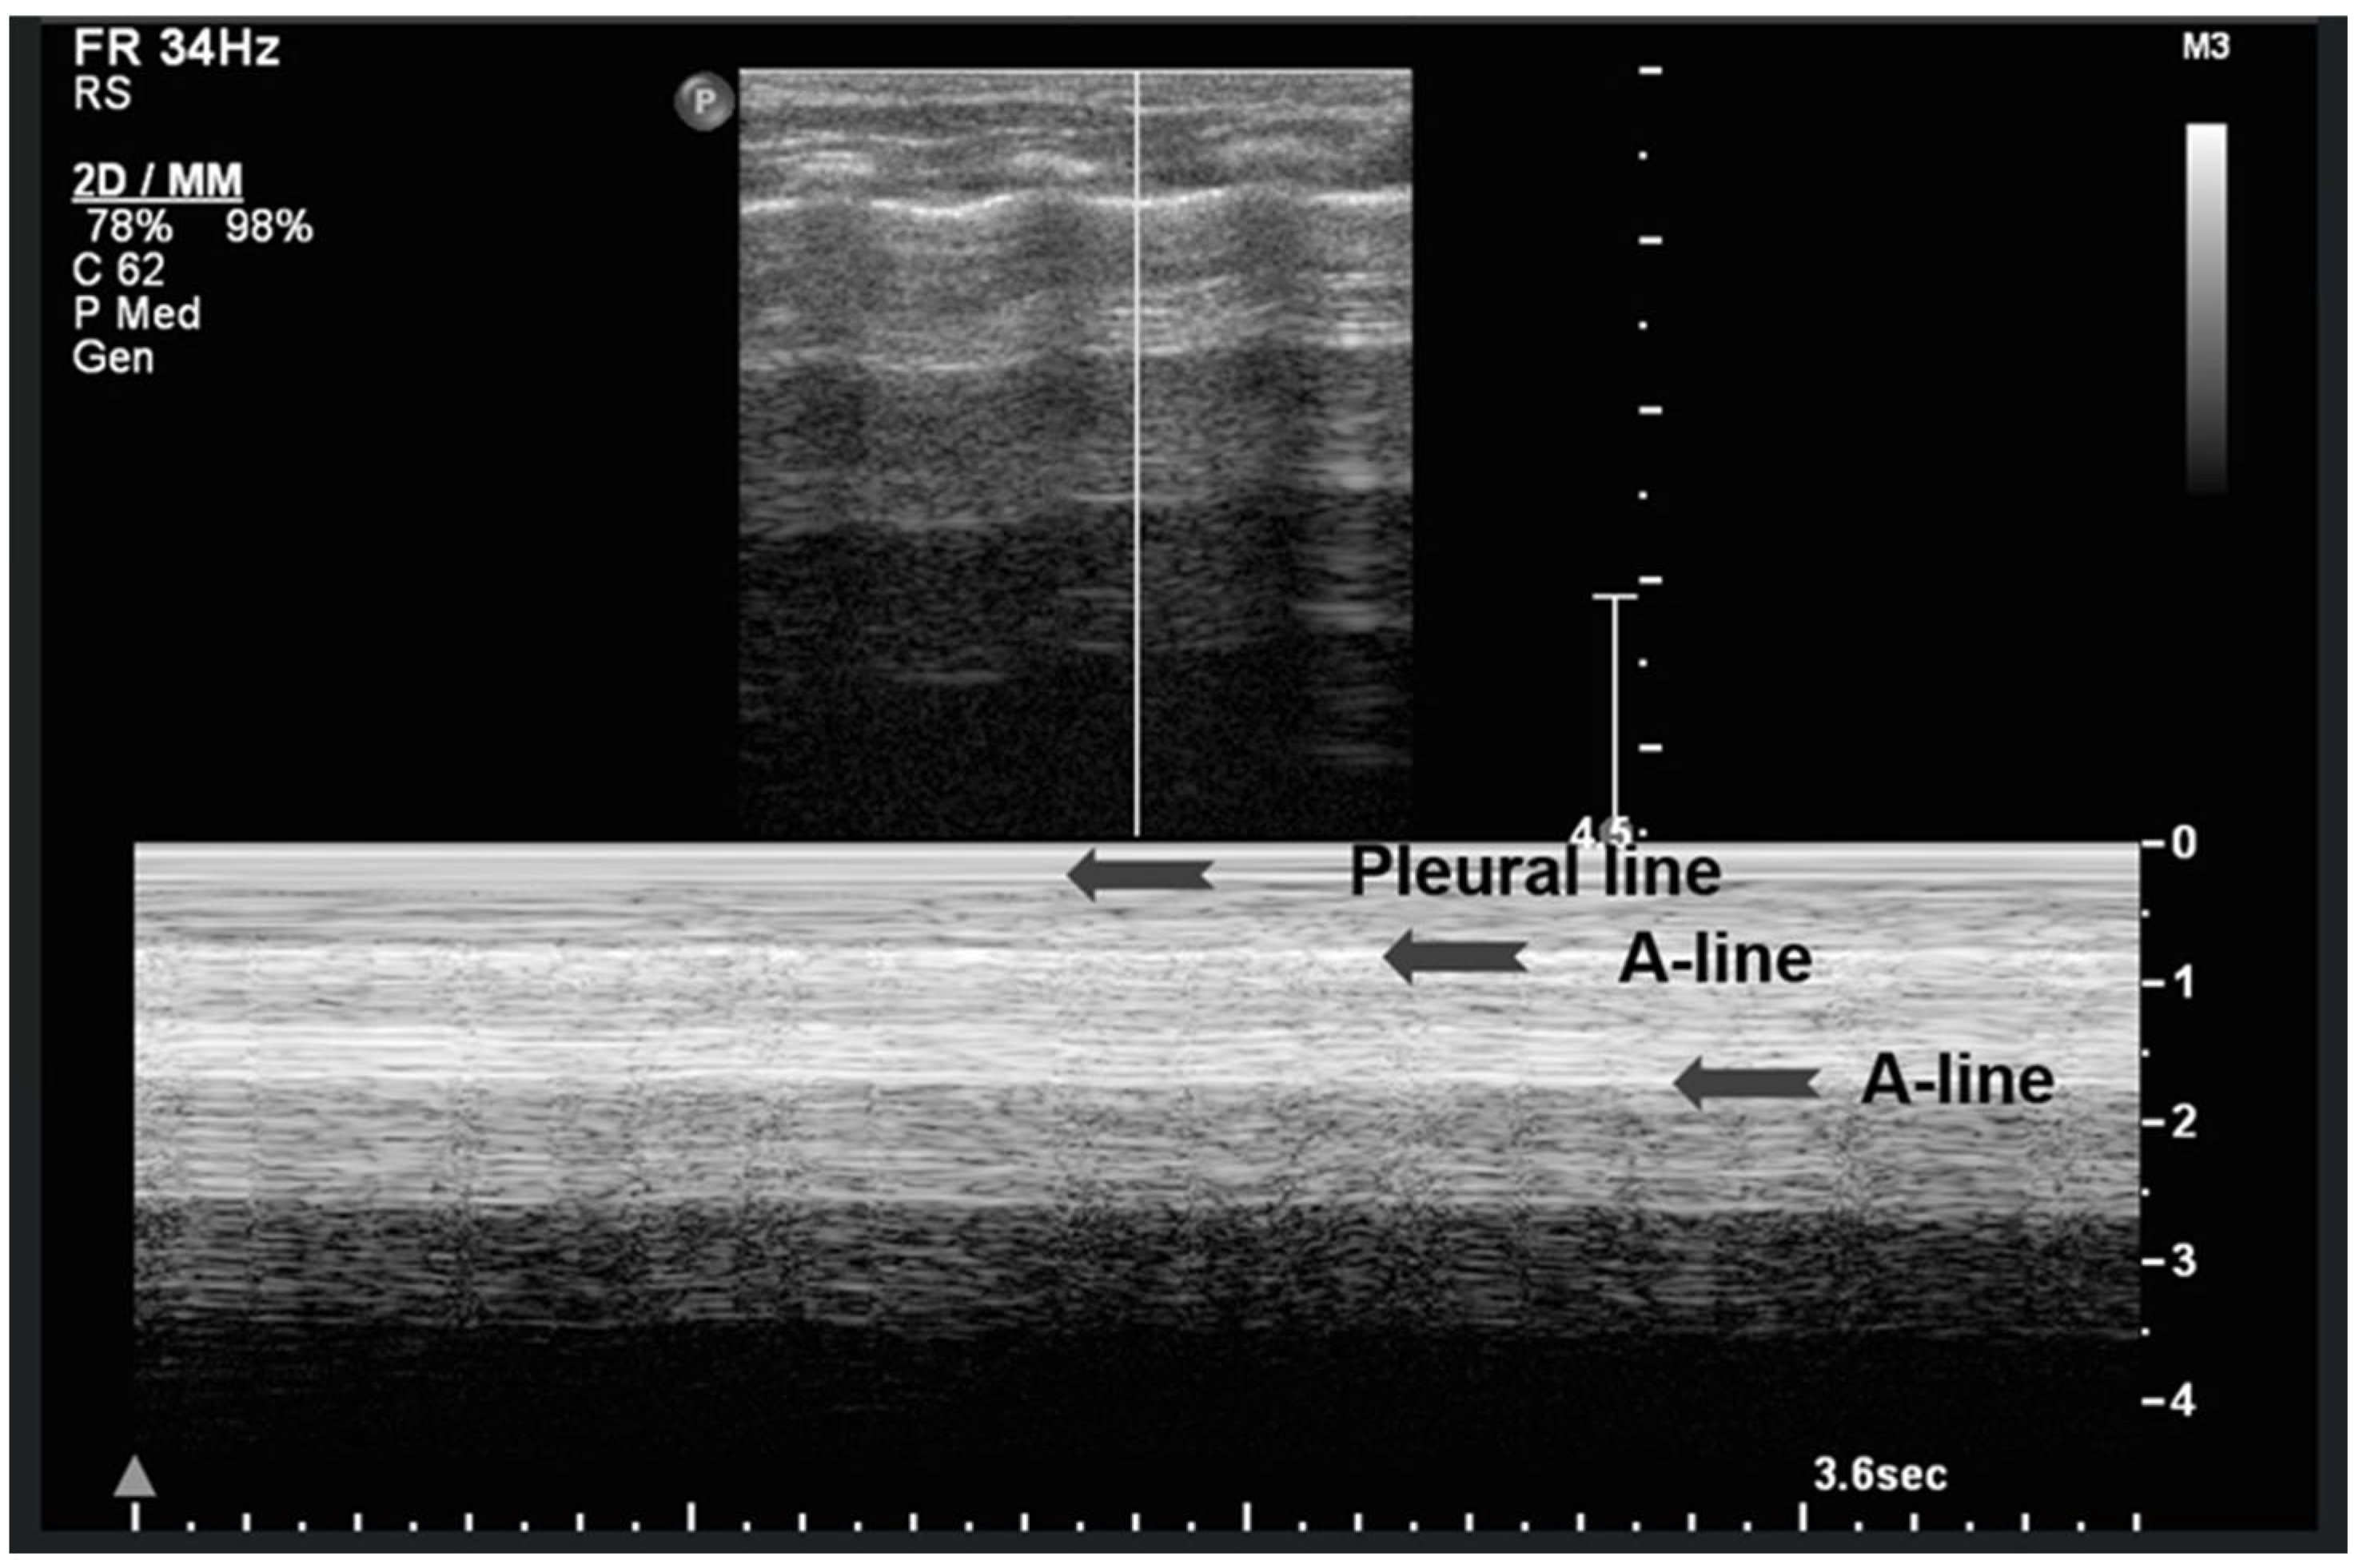

A-lines are horizontal, bright, echogenic lines that appear at equal intervals below the pleural line, running parallel to it (Figure 1). They are reverberation artifacts caused by the reflection of ultrasound waves between the pleura and the ultrasound probe. Although their presence typically indicates well-aerated, healthy lung tissue, A-lines can also be seen in certain pathological conditions, such as pneumothorax, where free air is present. Thus, A-lines are not always necessarily a sign of normal, healthy lungs [5,6,12,13,14,15,16].

Figure 1.

A-lines: Horizontal, bright, echogenic lines at equal intervals below the pleural line, running parallel to it. A-Lines are one of the main (basic) artifacts in LUS.

3.1.5. Sea-Shore Sign

The “sea-shore sign” is a characteristic ultrasound finding observed during M-mode (motion mode) scanning, and is indicative of normal lung sliding. In this pattern, the pleural line and overlying chest wall structures produce a series of horizontal echogenic lines, representing static tissues (Figure 6).

Figure 6.

Upper image: LUS with normal A-Lines in B (bright)-mode. The simultaneous M (motion)-mode image (lower image) reveals series of horizontal echogenic lines which represent the pleural line and its reverberations (A-lines), as well as the air-filled alveoli with a granular/sandy appearance (more prominent in real time scan). These in combination produce the seashore sign.

In contrast, the underlying lung parenchyma, which moves in synch with respiration, generates a granular or sandy appearance due to the dynamic motion of air-filled alveoli [17]. This combination creates the visual effect of waves (static layers) above and sand (with a dynamic speckled texture) below, thus producing the so-called “sea-shore sign”. The presence of this sign confirms normal apposition and movement of the visceral and parietal pleurae, and can be used to effectively rule out pneumothorax at the examination site. The “sea-shore sign” is considered to be a reliable and non-invasive indicator of intact lung sliding, and is frequently used in both adult and neonatal lung ultrasound to assess respiratory function and pleural integrity [5,6,15,22,23].

When this sign is absent, uniform horizontal straight lines, known as the stratosphere sign or “barcode sign”, appear, indicating pneumothorax as a possible cause [18,24].